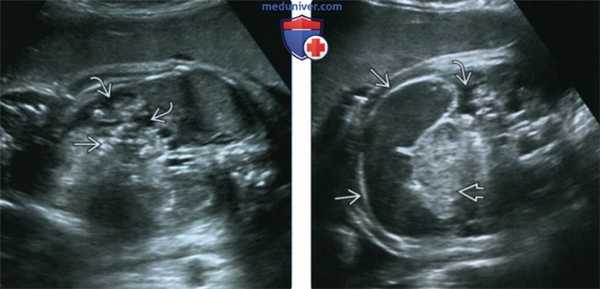

(Слева) УЗИ плода в 33 нед. Расчетный риск муковисцидоза (МВ) - 25%. Определяются незначительный асцит и умеренно гиперэхогенные петли кишечника.

(Справа) Тот же случай. Визуализируются признаки перфорации кишечника с мекониевым перитонитом: петля расширенного кишечника асцит, гиперэхогенный кишечник. В постнатальном периоде подтвержден диагноз муковисцидоза (МВ) и мекониевого перитонита. Несмотря на возможное совпадение ультразвуковой картины с атрезией подвздошной кишки, расширение дистального отдела тонкого кишечника следует всегда рассматривать как диагностический признак муковисцидоза (МВ).